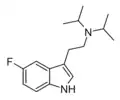

| 5-Fluoro-DMT | artificial | 5-F | CH3 | CH3 | 5-fluoro-N,N-dimethyltryptamine | 22120-36-1 |

| 5-Fluoro-MET | artificial | 5-F | CH3 | CH2CH3 | 5-fluoro-N-methyl-N-ethyltryptamine | |

| 5-Fluoro-DET | artificial | 5-F | CH2CH3 | CH2CH3 | 5-fluoro-N,N-diethyltryptamine | |

| 5-Fluoro-EPT | artificial | 5-F | CH2CH3 | CH2CH2CH3 | 5-fluoro-N-ethyl-N-propyltryptamine | |

| 5-Fluoro-DPT | artificial | 5-F | CH2CH2CH3 | CH2CH2CH3 | 5-fluoro-N,N-dipropyltryptamine | |

| 5-Fluoro-DiPT | artificial | 5-F | CH(CH3)2 | CH(CH3)2 | 5-fluoro-N,N-diisoproptryptamine | |